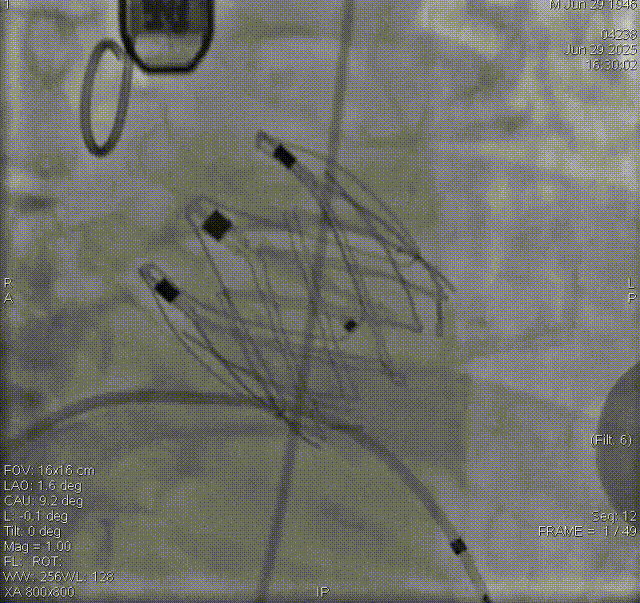

术前评估

术前影像评估提示,患者为典型三叶瓣结构,瓣窦分布均匀,无明显钙化,主动脉瓣环直径29.3mm,左室流出道直径30.6mm,STJ直径37.8mm,升主动脉直径40.5mm,双侧冠脉开口高度充足(左冠17.0mm,右冠27.6mm),无冠脉阻塞风险,左室-主动脉夹角137°,存在一定同轴性挑战。

CTA评估(上下滑动查看更多照片)

瓣膜选型:JS/TAVI-31瓣膜

术中回顾及效果

手术过程顺利。术中通过右窦居中造影、定位件入窦造影及释放后功能确认等关键步骤,确保瓣膜锚定准确。器械时间约10分钟。术中超声检查未见瓣周漏,瓣膜位置及功能评估良好,整个过程衔接紧密,无术中并发事件发生。术后即刻超声复查提示人工生物瓣启闭良好,平均跨瓣压差为6mmHg,血流速度正常。患者恢复情况稳定,心功能显著改善。

夹持件顺利入窦

术后造影